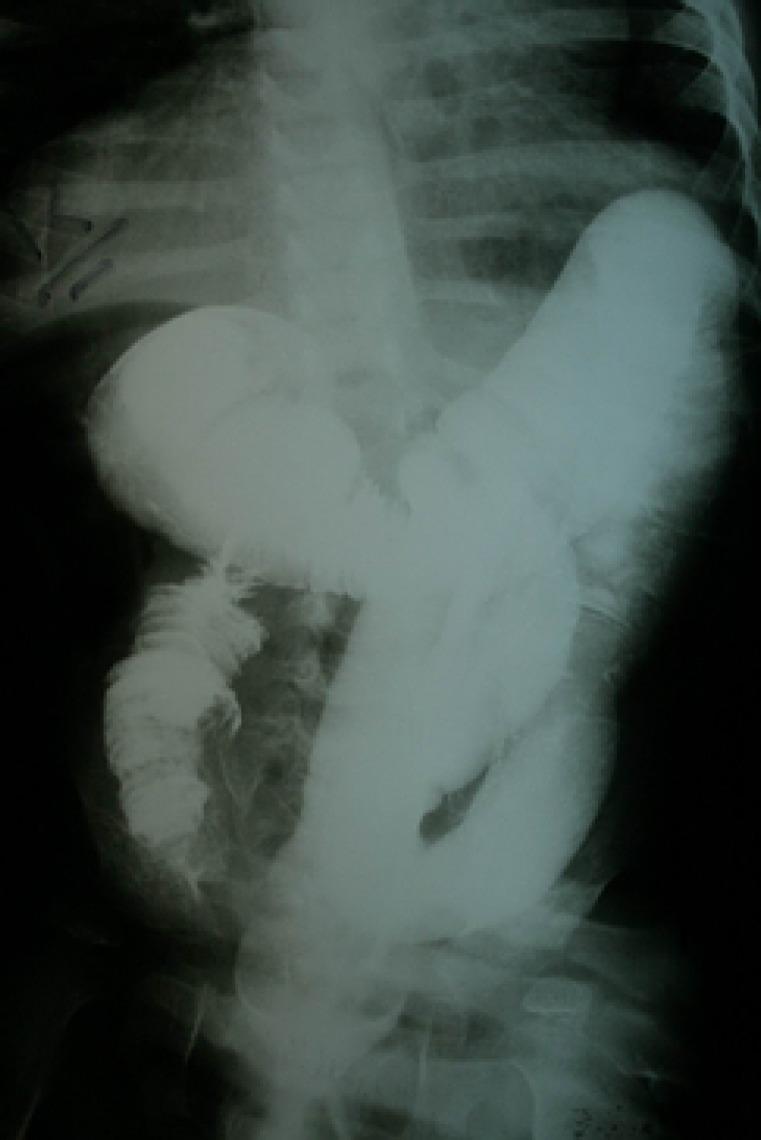

Schimke immuno-osseous dysplasia is a rare autosomal recessive multisystem disorder characterized by steroid-resistant nephrotic syndrome, immunodeficiency, and spondyloepiphyseal dysplasia. Mutations in SWI/SNF2 related, matrix associated, actin dependent regulator of chromatin, subfamily a-like 1 (SMARCAL1) gene are responsible for the disease. The present report describes, for the first time, a Schimke immuno-osseous dysplasia child with SMARCAL1 missense mutation (R561H) and manifestations of intussusception secondary to Epstein-Barr virus-negative non-Hodgkin lymphoma, who expired due to septicemia following chemotherapy. The report emphasizes the necessity of more limited immunosuppressive protocols in Schimke immuno-osseous dysplasia patients with lymphoproliferative disorders.

施姆克免疫性骨发育不良是一种罕见的常染色体隐性多系统疾病,其特征为类固醇抵抗性肾病综合征、免疫缺陷和脊椎骨骺发育不良。SWI/SNF2相关、基质相关、肌动蛋白依赖性染色质调节因子a样1(SMARCAL1)基因突变是导致该疾病的原因。本报告首次描述了一名患有SMARCAL1错义突变(R561H)的施姆克免疫性骨发育不良儿童,该儿童继发于爱泼斯坦-巴尔病毒阴性非霍奇金淋巴瘤的肠套叠,在化疗后因败血症死亡。该报告强调了对患有淋巴增殖性疾病的施姆克免疫性骨发育不良患者采用更有限的免疫抑制方案的必要性。